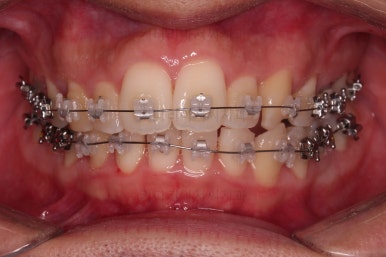

장치를 부착한 사진입니다.

이번 환자분이 부산앞니교정 선택하신 장치는 엠파워 클리어라고 하는 자가결찰(스스로 철사를 묶어주는 뚜껑이 달린) 세라믹 재질의 장치였어요.

흔히 클리피씨라고 알려진 종류의 장치인데요.

클리피는 일본장치, 엠파워는 미국장치, 제조사만 다를 뿐이고 큰 틀에서는 유사한 장치에요.

장치를 부착하고 철사를 주기적으로 바꿔주면서 치아를 가지런하게 해요.

장치를 부착한 직후의 모습입니다.

세라믹이라 비교적 밟아보이고 입술을 다물었을 때는 장치의 볼륨감으로 인해 약간은 입술이 더 불편해진 모습이에요.